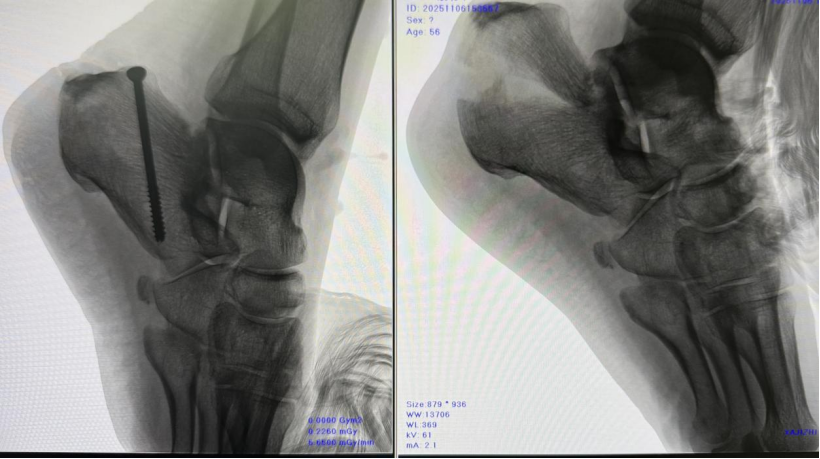

术前右足C型臂透视

患者俯卧位,抬高患肢,充分放松跟腱,于右足跟部外侧作三处约1cm切口,内侧作两处约1cm切口。

术中使用到钢丝引导器,从内侧切口处进入紧贴跟骨下骨面从外侧最下侧切口穿出,用一根单股超高分子量聚乙烯缝线穿入钢丝引导器将其引出,依次从各切口穿出,近端从跟腱下跟骨表面穿出,环绕跟骨一圈止于内侧切口,用单股超高分子量聚乙烯缝线带出一根双股超高分子量聚乙烯缝线环绕跟骨,各切口处留出约3-4cm长度缝线(方便于后期收紧缝线),用尖端复位钳通过后方小切口,一钳臂置于结节背侧,另一尖端穿过足跟脂垫,缓慢合拢钳臂,使骨折复位,透视下确认骨折复位可。

NICE结收紧缝线,用血管钳插入线圈,通过一挑一拉,逐渐拉紧收紧缝线,通过NICE结的滑动锁定机制实现动态加压,将导针自跟骨结节后下方钻入,透视确认导针位置满意后,沿导针拧入1枚φ4.5x50的空心金属接骨螺钉。最后将线头埋于皮下。再次透视确认骨折复位良好、内固定位置满意后,缝合切口,无菌敷料包扎。